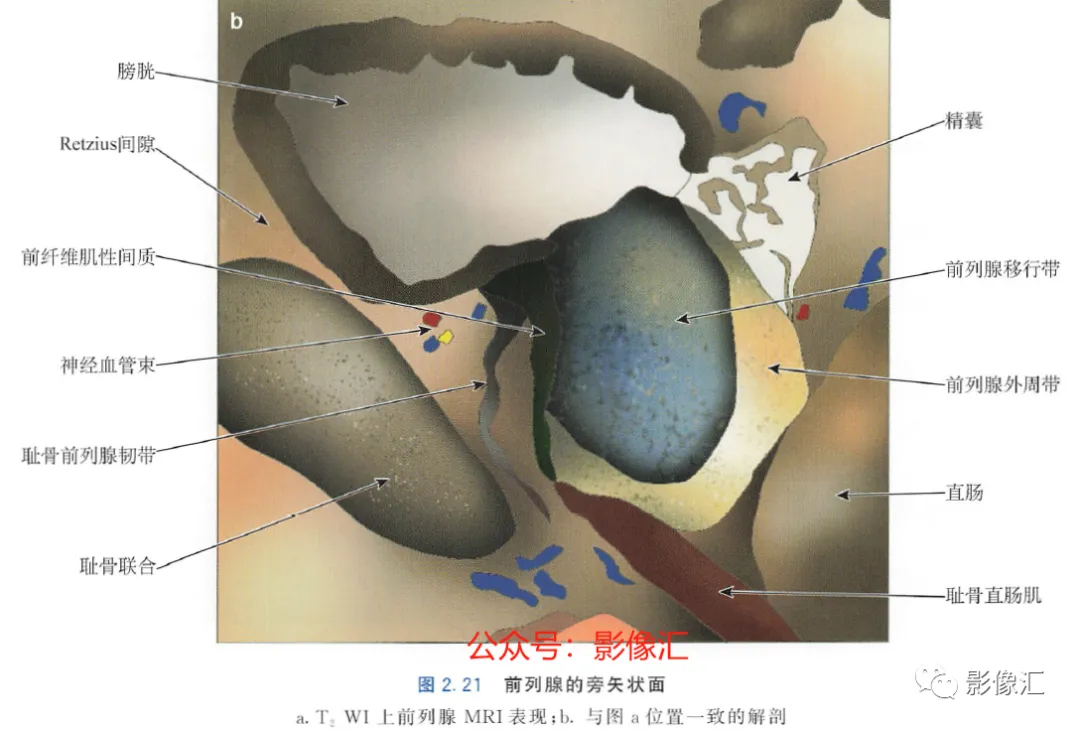

3.旁矢状面(图2.21)